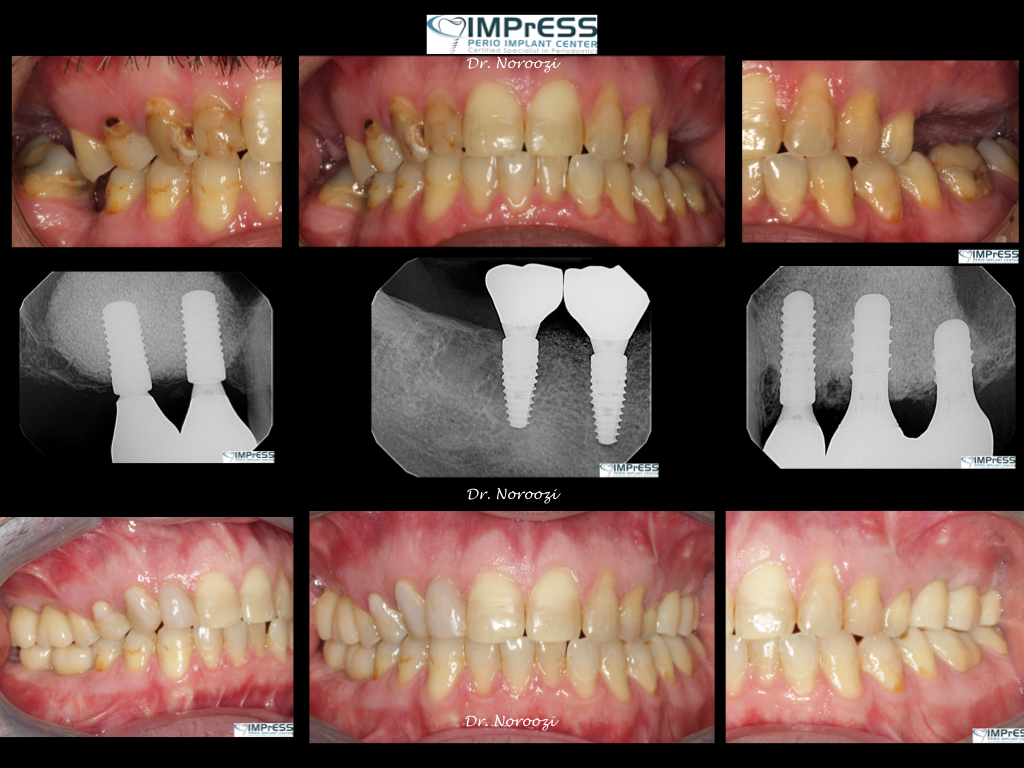

Sinus Lift Implant Vancouver Burnaby Periodontist Implant Dentist IMPreESS Perio

Dental Implant Centre in Vancouver Burnaby Sinus Lift Dental implant Surgery Dr. Noroozi Implant Specialist IMPrESS Perio Implant Center.001

Dr. Noroozi, certified periodontist in Burnaby, utilizes the most advanced technologies such as Piezosurgery to make your sinus lift surgery much safer, more effective and comfortable for you.

Dr. Noroozi Sinus Lift Surgery For Dental Implants IMPrESS Perio Implant Center

Sinus Lift, Bone Graft, Implants Dr. Noroozi IMPrESS Perio Implant Center